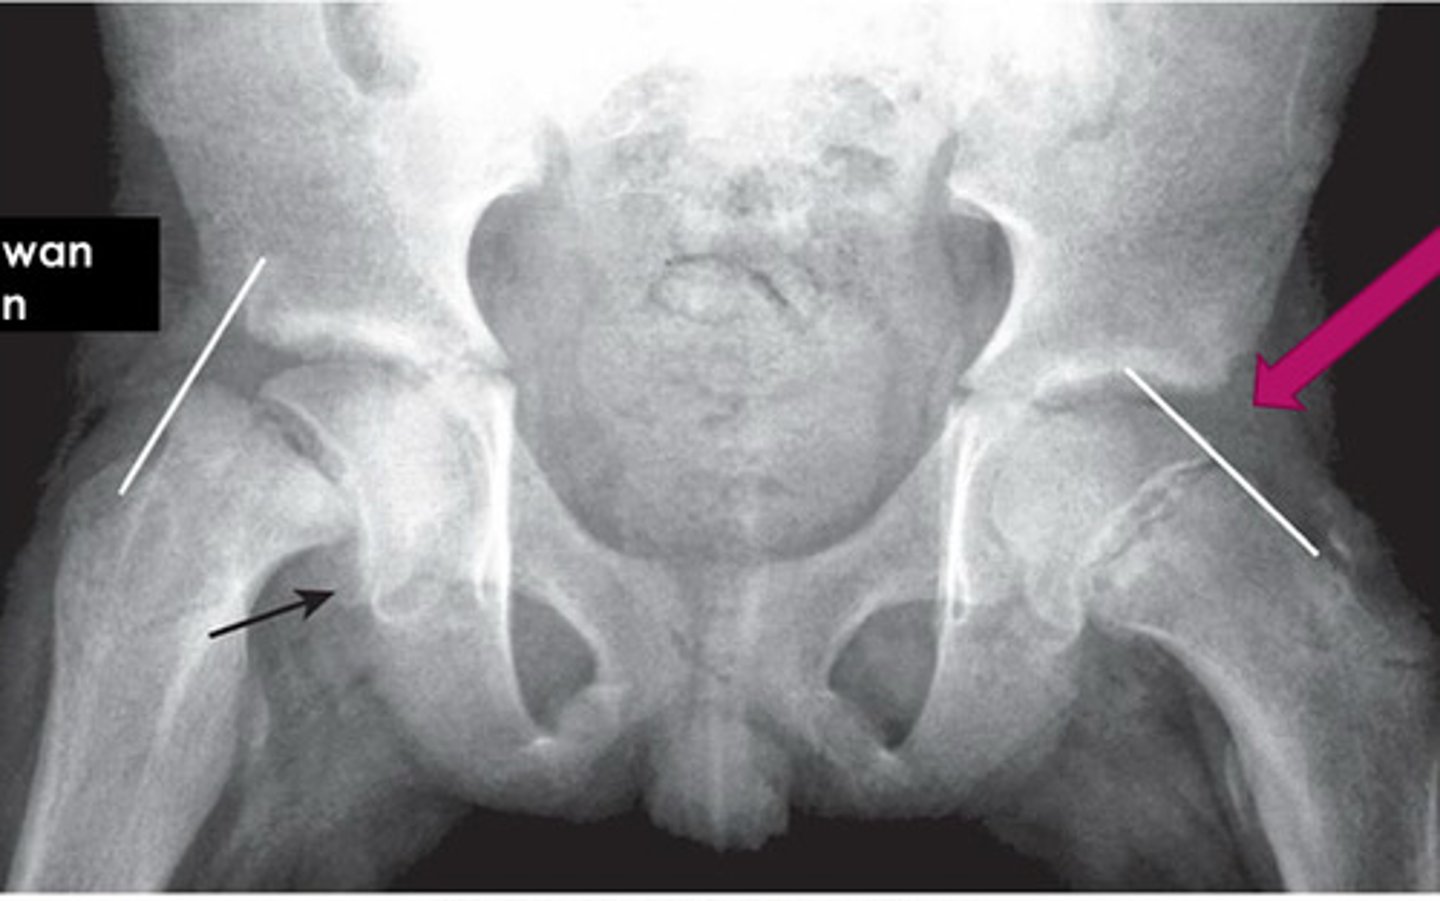

crescent sign

occurs when surface of articular surface is flattening (DO NOT MISS! PRECURSOR TO WORSENING DISEASE!)

pictured: AVN of femoral head